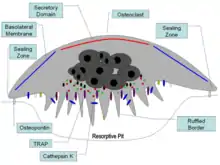

Osteoclast are multi-nucleated cells that that absorb and remove bone which is critical for growth of new bones and maintenance of bone strength. Osteoclasts are critical for the bone remodeling cycle which is achieved by the building of bone by osteoblasts, reabsorption by osteoclasts, and remodeling by osteoblasts.[10] Osteoclasts precursor cells and mature osteoclast require stimulation of CSF1R for survival. Blockage of CSF1R signaling prevents osteoclast precursor cells from proliferating, maturing, and fusing into multi-nucleated cells. Stimulation of CSF1R promotes osteoclastogenesis (differentiation of monocytes into osteoclasts). CSF1R signaling in osteoclasts precursors promotes survival by upregulation of the Bcl-X(L) protein, an inhibitor of pro-apoptotic caspase-9. CSF1R signaling in mature osteoclasts promotes survival by stimulating mTOR/S6 kinase and the Na/HCO3 co-transporter, NBCn1.[11] CSF1R signaling also directly regulates osteoclast function. Osteoclasts migrate along the bone surface, then adhere to the bone to degrade and reabsorb the bone matrix. CSF1R signaling positively regulates this behavior, increasing osteoclast chemotaxis and bone reabsorption.[10]

Bone remodeling is regulated by mutual cross-regulation between osteoclasts and osteoblasts. As a result, the dysfunction of CSF1R signaling directly affects the reabsorption (osteoclasts) and indirectly affects bone deposition (osteoblasts). In inflammatory arthritis conditions such as rheumatoid arthritis, psoriatic arthritis, and Crohn's disease, proinflammatory cytokine TNF-α is secreted by synovial macrophages which stimulates stromal cells and osteoblasts to produce CSF-1. Increased CSF-1 promotes proliferation of osteoclasts and osteoclast precursors and increases osteoclast bone reabsorption. This pathogenic increase in osteoclast activity causes abnormal bone loss or osteolysis.[14] In animal models of rheumatoid arthritis, administration of CSF-1 increases the severity of disease whereas Csf1r loss-of-function reduces inflammation and joint erosion.[10] In a rare bone disease called Gorham‐Stout disease, elevated production of CSF-1 by lymphatic endothelial cells similarly produces excessive osteoclastogenesis and osteolysis.[8] Additionally, postmenopausal loss of estrogen has also been found to impact CSF1R signaling and cause osteoporosis. Estrogen deficiency causes osteoporosis by upregulating production of TNF-α by activated T cells. As in inflammatory arthritis, TNF-α stimulates stromal cells to produce CSF-1 which increases CSF1R signaling in osteoclasts.[15]